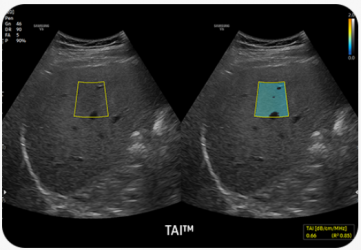

Kvantitativní měření jaterního tuku pomocí ultrazvuku |

TAI™ (Tissue Attenuation Imaging) umožňuje kvantitativní měření tkáňového útlumu pro hodnocení steatotických změn jater.

TSI™ (Tissue Scatter Distribution Imaging) umožňuje kvantitativní měření distribuce tkáňového rozptylu pro hodnocení steatotických změn jater.